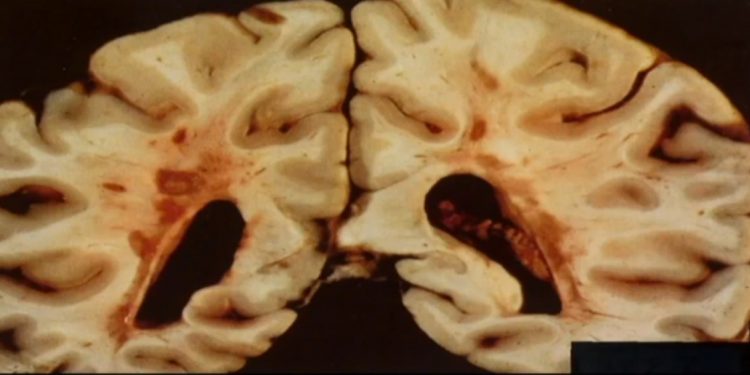

При неврологических заболеваниях, таких как рассеянный склероз, инсульт, травма головного мозга и болезнь Альцгеймера, гематоэнцефалический барьер разрушается. Когда это происходит, белки свертывания крови проникают в мозг и могут нанести ущерб. Тем не менее, неизвестно является ли разрыв гематоэнцефалического барьера результатом болезни или ее причиной. Доктор Акассоглу обнаружила, что один белок крови, в частности, фибриноген, вовлечен в рассеянный склероз и может использоваться для диагностики и лечения расстройства.